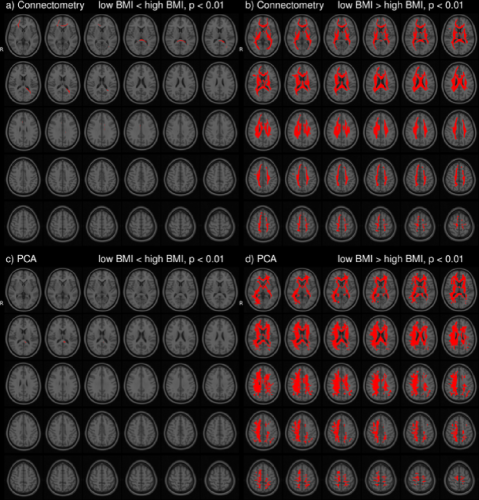

In the HCP dataset, ODFs correlate strongly with the demographic variable BMI. As expected, the ODFs negatively correlate (Fig. 7b) with BMI, indicating a loss of anisotropy with increasing BMI (Fig. 5a,b). This result is consistent with the well-established negative association between global white matter integrity and physical obesity (Mueller et al., 2011; Stanek et al., 2011; Verstynen et al., 2012; Gianaros et al., 2013; Verstynen et al., 2013). The fiber directions (Fig. 8a,b) identified from can be used to perform tractography (Fig. 8c,d). Resulting tracts (Fig. 8c,d) show a pronounced loss of anisotropy in the corticospinal tracts, the optic radiations and the right superior longitudinal fasciculus. These results are corroborated by the existing methods TBSS (Fig. 9a,b, S2a,b), Connectivity-based fixel enhancement (Fig. 9c,d, S2c,d) and local connectometry (Fig. 9e,f, S3a,b). The volume of positive findings of correlation with BMI is largest when using the full ODF information with the ODF approach (Fig. 9). In addition, in a test of specificity, no voxels are found to correlate with randomly permuted BMI (Fig. S4).

Several methods exist to analyze populations of diffusion MRI datasets, typically working on a reduced dimensionality subset of the diffusion data. TBSS (Jbabdi et al., 2010), limiting the analysis to a projection to a tract skeleton, succeeds in identifying the tracts most significantly correlated with BMI (analysis of FA, Fig. 9a,b, S2a,b) but misses the full extent of the correlations. The Connectivity-based fixel enhancement (Raffelt et al., 2015) and Connectometry (Yeh et al., 2016) approaches do include more of the available information and hence perform better than the TBSS method (Fig. 9c,d, S2c,d (Fixel enhancement) and 9e,f, S3a,b (Connectometry) vs 9a,b, S2a,b (TBSS)).

None of the above methods however capitalizes on the full ODF information. This in contrast to the approach presented in this paper. The ODF approach indeed identifies a larger volume of significant findings (227 cm3) than the existing methods tested here (TBSS 17 cm3, Connectivity-based fixel enhancement 15 cm3 and Connectometry 212 cm3, Fig. 9b,d,f,h,j). That is, by analyzing the full ODF information and not reducing the dimensionality of the diffusion data, as is commonly done, the ODF approach is able to pick up on smaller significant changes, better grasping the full extent of the significant findings. Limitations on computational power and diffusion acquisitions (e.g. DTI) which inspired the data reduction of older methods no longer exist. It is hence advisable to maximize the amount of information included in the analysis as in the approach presented here.